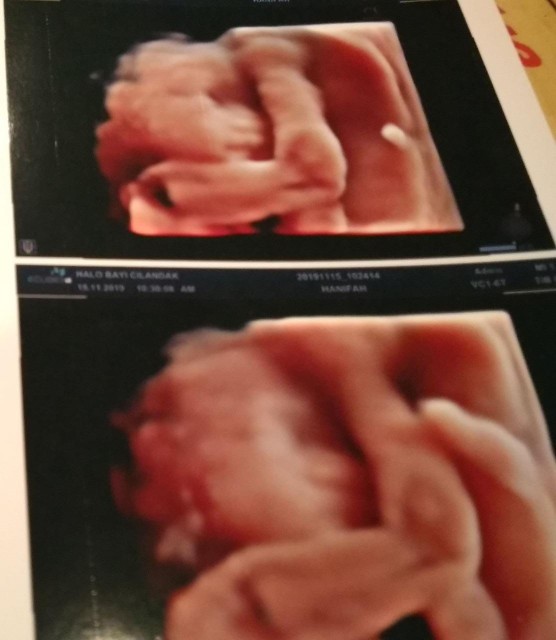

Waktu Usg 4d pas 7bln , lucunya baby yg msh dlm perut udh bisa ngemutin jari๐ Dan alhamdulilah skrg baby nya udh lahir prempuan dgn berat 3,35